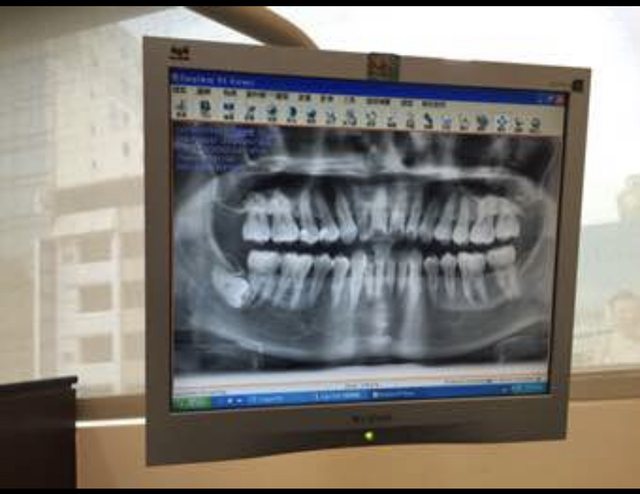

去看醫生照X光他傻眼

https://i.imgur.com/82aIEpj.jpg

他說你的旁邊有一顆完整成長

橫躺的智齒噎

你都不會痛嗎

我說完全沒有感覺

→ PnPn : 你的牙醫是來搞笑的吧…那顆那麼深 27.51.64.26 09/17 19:15

→ PnPn : 在骨頭裡本來就不會有什麼問題 27.51.64.26 09/17 19:15